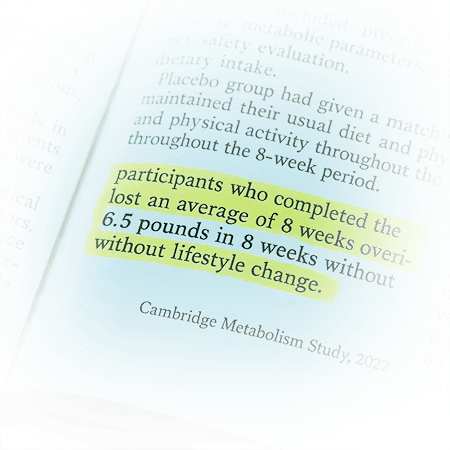

Study after study.

In a Cambridge-led double-blind, placebo- controlled trial, participants taking RS2 ... a rare resistant starch ... lost an average of 6.5 pounds in just 8 weeks…

Without changing their diet or routine.

And researchers discovered why: RS2 didn't just improve gut health…

It reactivated a hidden fat-command system that controls metabolism at the cellular level.

Without changing anything else about their diet.

Women lost an average of 6.5 pounds in just 8 weeks without changing anything else.